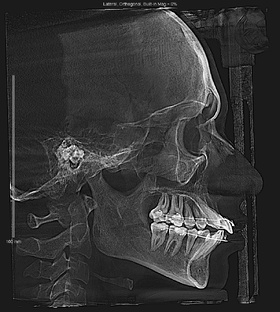

История пациента: сильная суставная боль и заваленная назад челюсть

Наша сегодняшняя героиня — Елена, 45 лет. Елена обратилась к нам с жалобами на сильную суставную боль. В подростковом возрасте она уже проходила ортодонтическое лечение, но, тем не менее, ее верхняя челюсть была сильно завалена назад, что, в конечном счете, и вызывало боли. Пациентка обратилась к нам с жалобами на сильную суставную боль: болезненные ощущения возникали каждый раз при смыкании и размыкании челюстей. В процессе первичного опроса выяснилось, что в подростковом возрасте Елена проходила ортодонтическое лечение...